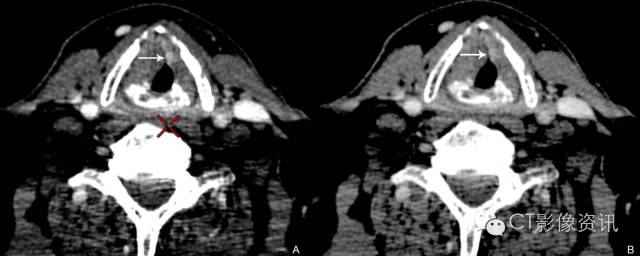

57岁男性 喉癌患者,单能图像较混合能量图像更清晰显示较小病变(左图为常规混合能量图像)。